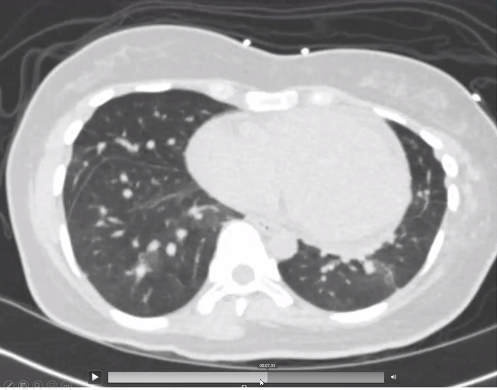

She goes to the ED and gets another CT... mosaicism is still there but now she has a new bilateral pleural effusions and interlobular septal thickening and atelectasis.

So both the plot, and the interlobular septa, have thickened.